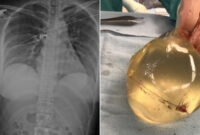

Q&A: PIP Breast Implants Health Scare – BBC News

www.bbc.com

breast implants implant pip health scare